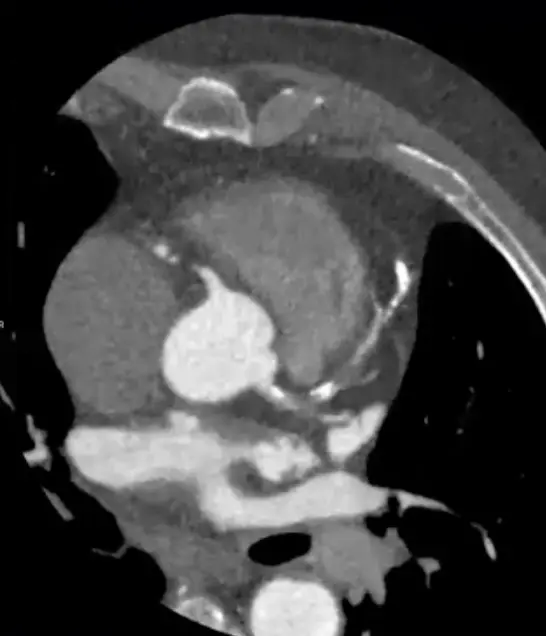

• 2 main coronary arteries that arise from the aorta

• Coronary artery origins/ostia

• RCA comes off of the RCC and heads anteriorly (towards the sternum)

• LM comes off of the LCC

Right coronary artery

• Travels along the atrioventricular groove around the acute margin of the heart.